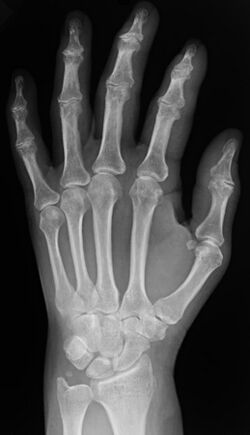

Plain x-ray of the wrist and hand

In the clinical context, "invisible light" medical imaging is generally equated to radiology or "clinical imaging". "Visible light" medical imaging involves digital video or still pictures that can be seen without special equipment. Dermatology and wound care are two modalities that use visible light imagery. Interpretation of medical images is generally undertaken by a physician specialising in radiology known as a radiologist; however, this may be undertaken by any healthcare professional who is trained and certified in radiological clinical evaluation. Increasingly interpretation is being undertaken by non-physicians, for example radiographers frequently train in interpretation as part of expanded practice. Diagnostic radiography designates the technical aspects of medical imaging and in particular the acquisition of medical images. The radiographer (also known as a radiologic technologist) is usually responsible for acquiring medical images of diagnostic quality; although other professionals may train in this area, notably some radiological interventions performed by radiologists are done so without a radiographer.[citation needed]

Two forms of radiographic images are in use in medical imaging. Projection radiography and fluoroscopy, with the latter being useful for catheter guidance. These 2D techniques are still in wide use despite the advance of 3D tomography due to the low cost, high resolution, and depending on the application, lower radiation dosages with 2D technique. This imaging modality uses a wide beam of x rays for image acquisition and is the first imaging technique available in modern medicine.

• Projectional radiographs, more commonly known as x-rays, are often used to determine the type and extent of a fracture as well as for detecting pathological changes in the lungs. With the use of radio-opaque contrast media, such as barium, they can also be used to visualize the structure of the stomach and intestines – this can help diagnose ulcers or certain types of colon cancer.[citation needed]